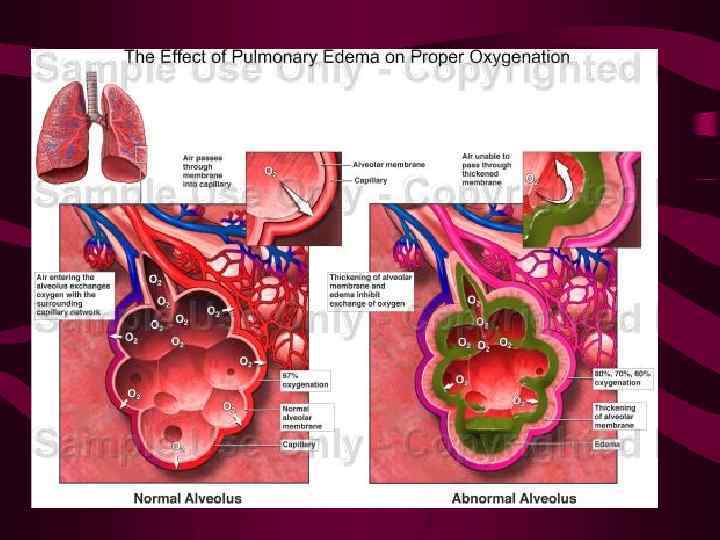

ОТЕК ЛЕГКИХ патологическое состояние, возникающее в результате накопления в легочной ткани избыточного количества внесосудистой жидкости

ОТЕК ЛЕГКИХ патологическое состояние, возникающее в результате накопления в легочной ткани избыточного количества внесосудистой жидкости

Объем внесосудистой жидкости в легком может увеличиваться в результате действия четырех патофизиологических фокторов: 1. Повышения гидростатического давления в легочных капилярах 2. Повреждения стенок легочных капиляров 3. Снижения осмотического (онкотического) давления крови 4. Замедления или прекращение лимфооттока Последние два фактора не имеют самостоятельного значения в развитии отека легких.

Объем внесосудистой жидкости в легком может увеличиваться в результате действия четырех патофизиологических фокторов: 1. Повышения гидростатического давления в легочных капилярах 2. Повреждения стенок легочных капиляров 3. Снижения осмотического (онкотического) давления крови 4. Замедления или прекращение лимфооттока Последние два фактора не имеют самостоятельного значения в развитии отека легких.

В зависимости от того в каких анатомических структурах накапливается избыточная внесосудистая жидкость, различают отеки: интерстициальные альвеолярные

В зависимости от того в каких анатомических структурах накапливается избыточная внесосудистая жидкость, различают отеки: интерстициальные альвеолярные

Патогенетический механизм развития гидростатического отека Повышение гидростатического давления крови в легочных капиллярах → объем жидкости, проникающей из них в интерстициальные пространства увеличивается. Венозные и лимфатические сосуды не в состоянии удалить избыточное количество этой жидкости, что и приводит к развитию отека. Внесосудистая жидкость первоначально накапливается в интерстициальных пространтсвах. После того, как все резервные возможности легочного интерстиция оказываются исчерпаны, начинается заполнение альвеол.

Патогенетический механизм развития гидростатического отека Повышение гидростатического давления крови в легочных капиллярах → объем жидкости, проникающей из них в интерстициальные пространства увеличивается. Венозные и лимфатические сосуды не в состоянии удалить избыточное количество этой жидкости, что и приводит к развитию отека. Внесосудистая жидкость первоначально накапливается в интерстициальных пространтсвах. После того, как все резервные возможности легочного интерстиция оказываются исчерпаны, начинается заполнение альвеол.